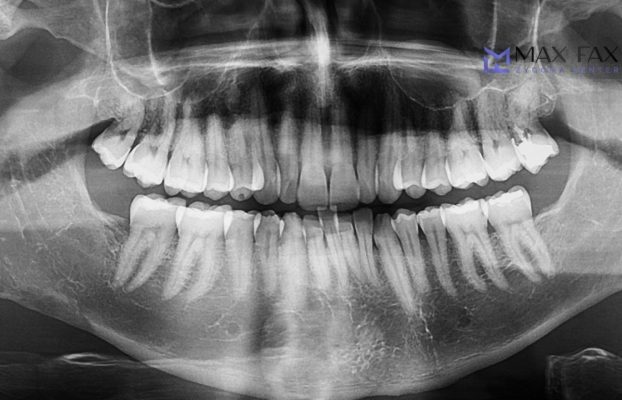

Zygoma implants offer durable and reliable implant solutions placed in the cheekbones for patients with jaw bone deficiency. It is an ideal treatment option for a healthy and aesthetic smile.

Zygoma implant is also known as cheekbone implant. There is general information about the zygoma implant, which is the most effective treatment method for patients who have permanently lost their teeth. The curious details about the increasingly popular treatment are as follows: